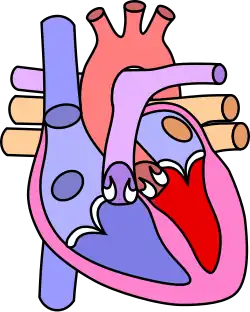

Diagram of a healthy heart and one with tetralogy of Fallot | |

Tetralogy of Fallot (TOF), formerly known as Steno-Fallot tetralogy,[9] is a congenital heart defect characterized by four specific cardiac defects.[4] Classically, the four defects are:[4]

- Pulmonary stenosis, which is narrowing of the exit from the right ventricle;

- A ventricular septal defect, which is a hole allowing blood to flow between the two ventricles;

- Right ventricular hypertrophy, which is thickening of the right ventricular muscle; and

- an overriding aorta, which is where the aorta expands to allow blood from both ventricles to enter.

Four malformations

"Tetralogy" denotes four parts, here implying the syndrome's four anatomic defects.[2] This is not to be confused with the similarly named teratology, a field of medicine concerned with abnormal development and congenital malformations (including tetralogy of Fallot). Below are the four heart malformations that present together in tetralogy of Fallot:

Pulmonary Infundibular Stenosis | A narrowing of the right ventricular outflow tract. It can occur at the pulmonary valve (valvular stenosis) or just below the pulmonary valve (infundibular stenosis).[4] Infundibular pulmonic stenosis is mostly caused by the overgrowth of the heart muscle wall (hypertrophy of the septoparietal trabeculae),[42] however, the events leading to the formation of the overriding aorta are also believed to be a cause. The pulmonic stenosis is the major cause of the malformations, with the other associated malformations acting as compensatory mechanisms to the pulmonic stenosis.[43] The degree of stenosis varies between individuals with TOF and is the primary determinant of symptoms and severity. This malformation is infrequently described as sub-pulmonary stenosis or subpulmonary obstruction.[44] |

Overriding aorta | An aortic valve with biventricular connection, that is, it is situated above the ventricular septal defect and connected to both the right and the left ventricle. The degree to which the aorta is attached to the right ventricle is referred to as its degree of "override." The aortic root can be displaced toward the front (anteriorly) or directly above the septal defect, but it is always abnormally located to the right of the root of the pulmonary artery. The degree of override is extremely variable, with 5–95% of the valve being connected to the right ventricle.[42] |

Ventricular septal defect (VSD) | A hole between the two bottom chambers (ventricles) of the heart. The defect is centered around the most superior aspect of the ventricular septum (the outlet septum), and in the majority of cases is single and large. In some cases, thickening of the septum (septal hypertrophy) can narrow the margins of the defect.[42] |

Right ventricular hypertrophy | The right ventricle is more muscular than normal, causing a characteristic boot-shaped (coeur-en-sabot) appearance as seen by chest X-ray. Due to the misarrangement of the external ventricular septum, the right ventricular wall increases in size to deal with the increased obstruction to the right outflow tract. This feature is now generally agreed to be a secondary anomaly, as the level of hypertrophy tends to increase with age.[45] |